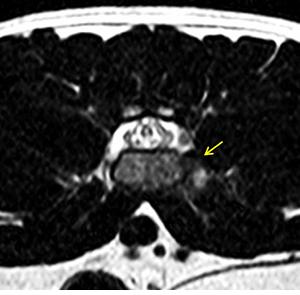

연구 대상은 4세 장모 고양이로 갑작스러운 좌측 후지 절뚝거림과 점프 회피 증상을 보였다. MRI 검사 결과, L6–L7 추간판이 원외측으로 탈출해 신경근을 압박하고, 국소 염증을 동반한 사실이 밝혀졌다. 이는 지금까지 개에서만 드물게 보고된 질환으로 고양이에서는 최초 사례다.